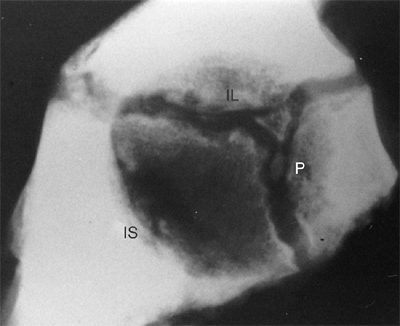

![]() |

Figure 24.3

Coronal section through the center of the acetabulum in a full-term infant. Note the fibrocartilaginous edge of the acetabulum, the labrum (arrows), at the peripheral edge of the acetabular cartilage. The hip capsule inserts just above the labrum. |

Figure 24.4

Lateral radiograph of the acetabulum of a 9-year-old girl. Two centers of ossification are seen within the cartilage adjoining the pubis (P) and appear to be developing within the vertical phalange of the triradiate cartilage. The positions of the ischium (IS) and the ilium (IL) are indicated. (From Ponseti IV. Growth and development of the acetabulum in the normal child: anatomical, histological and roentgenographic studies. J Bone Joint Surg Am 1978;60:575.) |